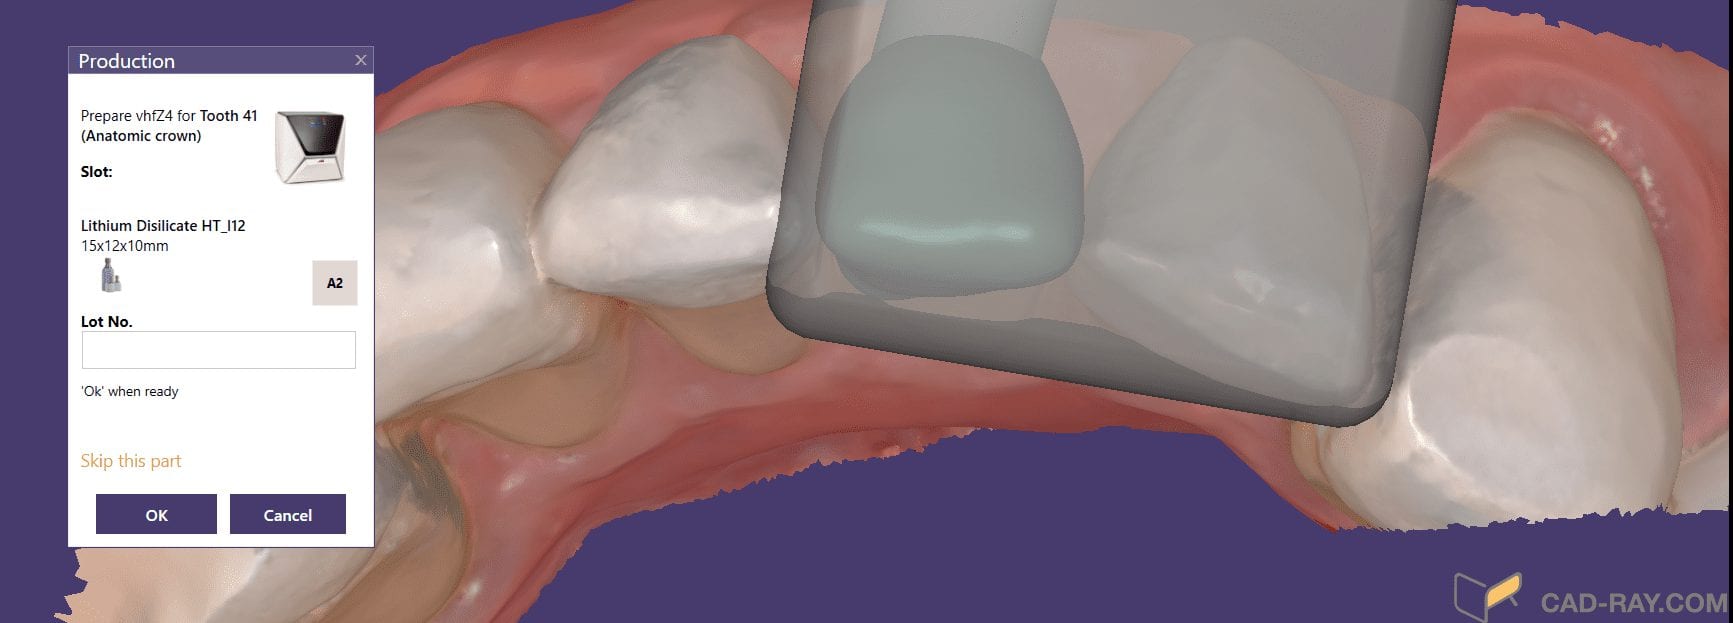

Milling A Lower Central Incisor in an eMax Size 12 Block on the VHF Z4 Milling Machine

March 29, 2019Time Stamps: This video is sped up at some points, but from the time the design was finished and it was sent to production, it tool less than 90 seconds […]